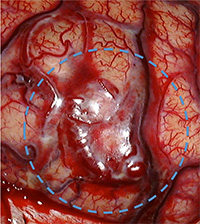

手術中の血管奇形部分の写真。青丸部分に拡張した血管網が見られます。(下図)